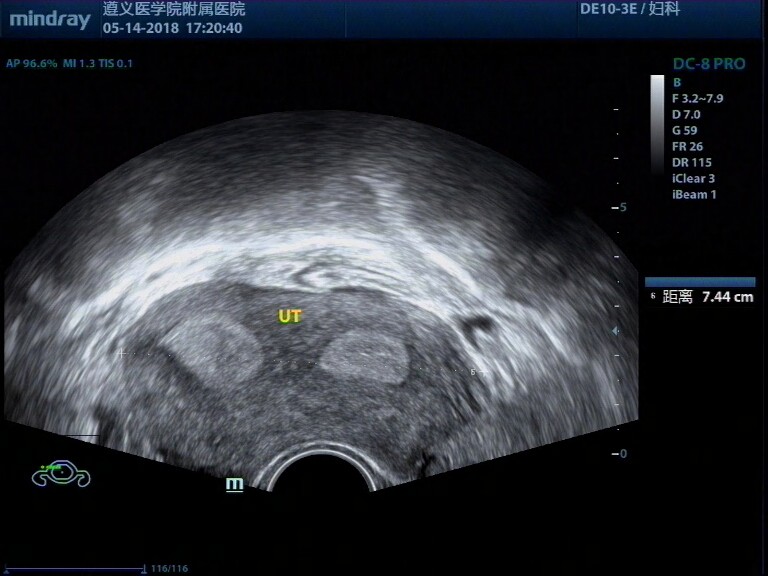

病例,31岁女性,纵膈子宫、畸胎瘤、子宫肌瘤

病例,31岁女性,纵膈子宫、畸胎瘤、子宫肌瘤。

病例来源遵义医学院附属医院